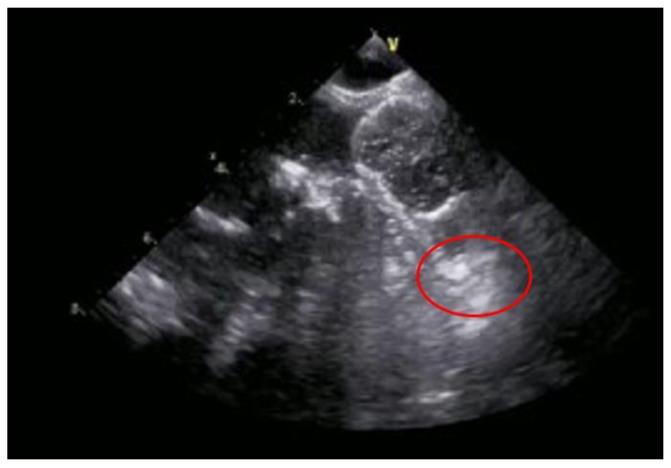

抗血栓治疗失败患者的左心耳封堵术:早期研究带来的积极信号

Left Atrial Appendage Occlusion in Patients with Failure of Antithrombotic Therapy: Good Vibes from Early Studies.

心房颤动(AF)是最常见的持续性心律失常,会使患者发生心脏栓塞事件(CE)的风险增加,如缺血性中风、短暂性脑缺血发作(TIA)或全身性栓塞[...]。